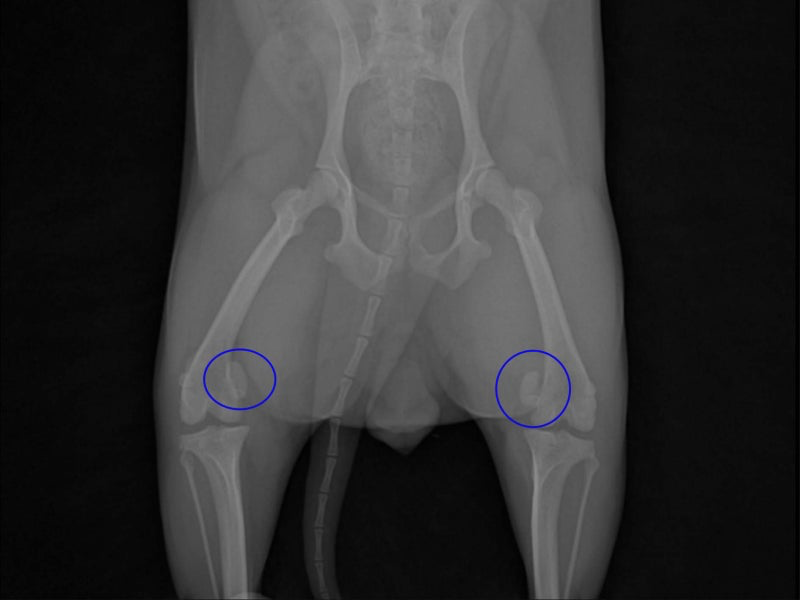

수술 전 환자의 방사선 사진

수술 전 방사선 사진에서, 동그라미 쳐 놓은 부분이 슬개골입니다. 현재 안쪽으로 많이 돌아가있습니다.

안쪽으로 돌아가 있는 것을 슬개골 탈구 내측탈구이며, 바깥쪽으로 돌아간 외측탈구에 비해 흔한편입니다.